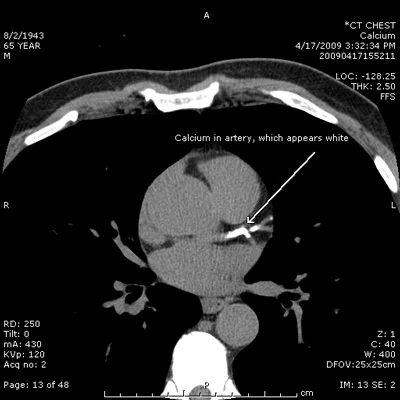

Koroner kalsiyum skoru, kontrastsız kardiyak bilgisayarlı tomografi (BT) ile ölçülür. Görüntüleme sırasında koroner arterlerdeki kalsifiye alanlar tespit edilir ve yoğunluklarına göre puanlandırılır.

Bu puanlama sistemi, en yaygın olarak Agatston skoru üzerinden yapılır. Agatston yöntemi, kalsifiye plakların hem yüzey alanını hem de yoğunluğunu dikkate alarak toplam bir skor oluşturur.